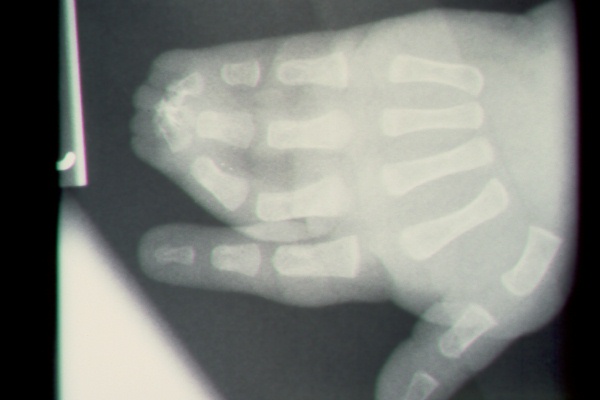

Clinical Example: Syndactyly

syndactyly